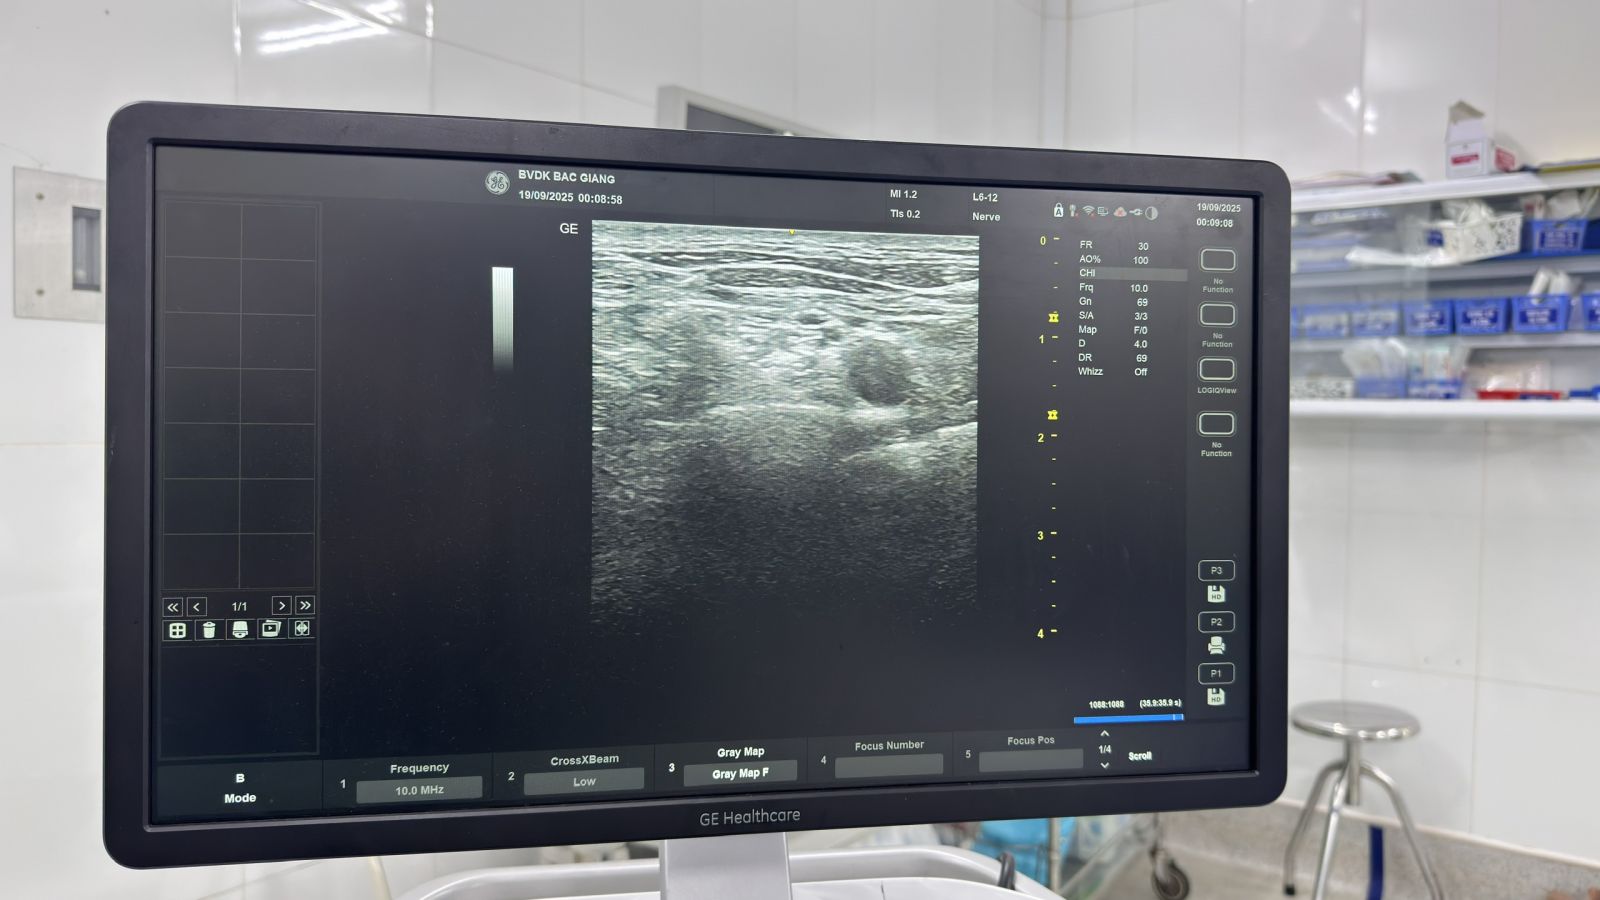

Với mục tiêu không ngừng nâng cao chất lượng điều trị và chăm sóc người bệnh, khoa Phẫu thuật – Gây mê Hồi sức, Bệnh viện Đa khoa Bắc Ninh số 1 đã triển khai và làm chủ kỹ thuật gây tê vùng dưới hướng dẫn siêu âm, đặc biệt là gây tê đám rối thần kinh cánh tay. Kỹ thuật này giúp bác sĩ quan sát trực tiếp cấu trúc thần kinh, cơ và mạch máu trên màn hình siêu âm - từ đó đưa kim và thuốc tê chính xác vào vị trí mong muốn, đảm bảo an toàn, chính xác và hiệu quả giảm đau tối ưu cho bệnh nhân.

BS. Nguyễn Văn Cường – Phó Trưởng khoa Phẫu thuật - Gây mê Hồi sức chi sẻ: “Gây tê dưới hướng dẫn siêu âm là xu thế tất yếu trong gây mê hồi sức hiện đại. Nhờ hình ảnh siêu âm, bác sĩ có thể xác định chính xác vị trí thần kinh, giúp kỹ thuật đạt độ chính xác gần như tuyệt đối, giảm đáng kể biến chứng và nâng cao an toàn cho người bệnh. Đây là bước tiến quan trọng giúp bệnh nhân giảm đau hiệu quả, sớm hồi phục và là hướng đi mà khoa đang tiếp tục mở rộng cho nhiều vùng khác như chi dưới, ngực, bụng… trong thời gian tới.”